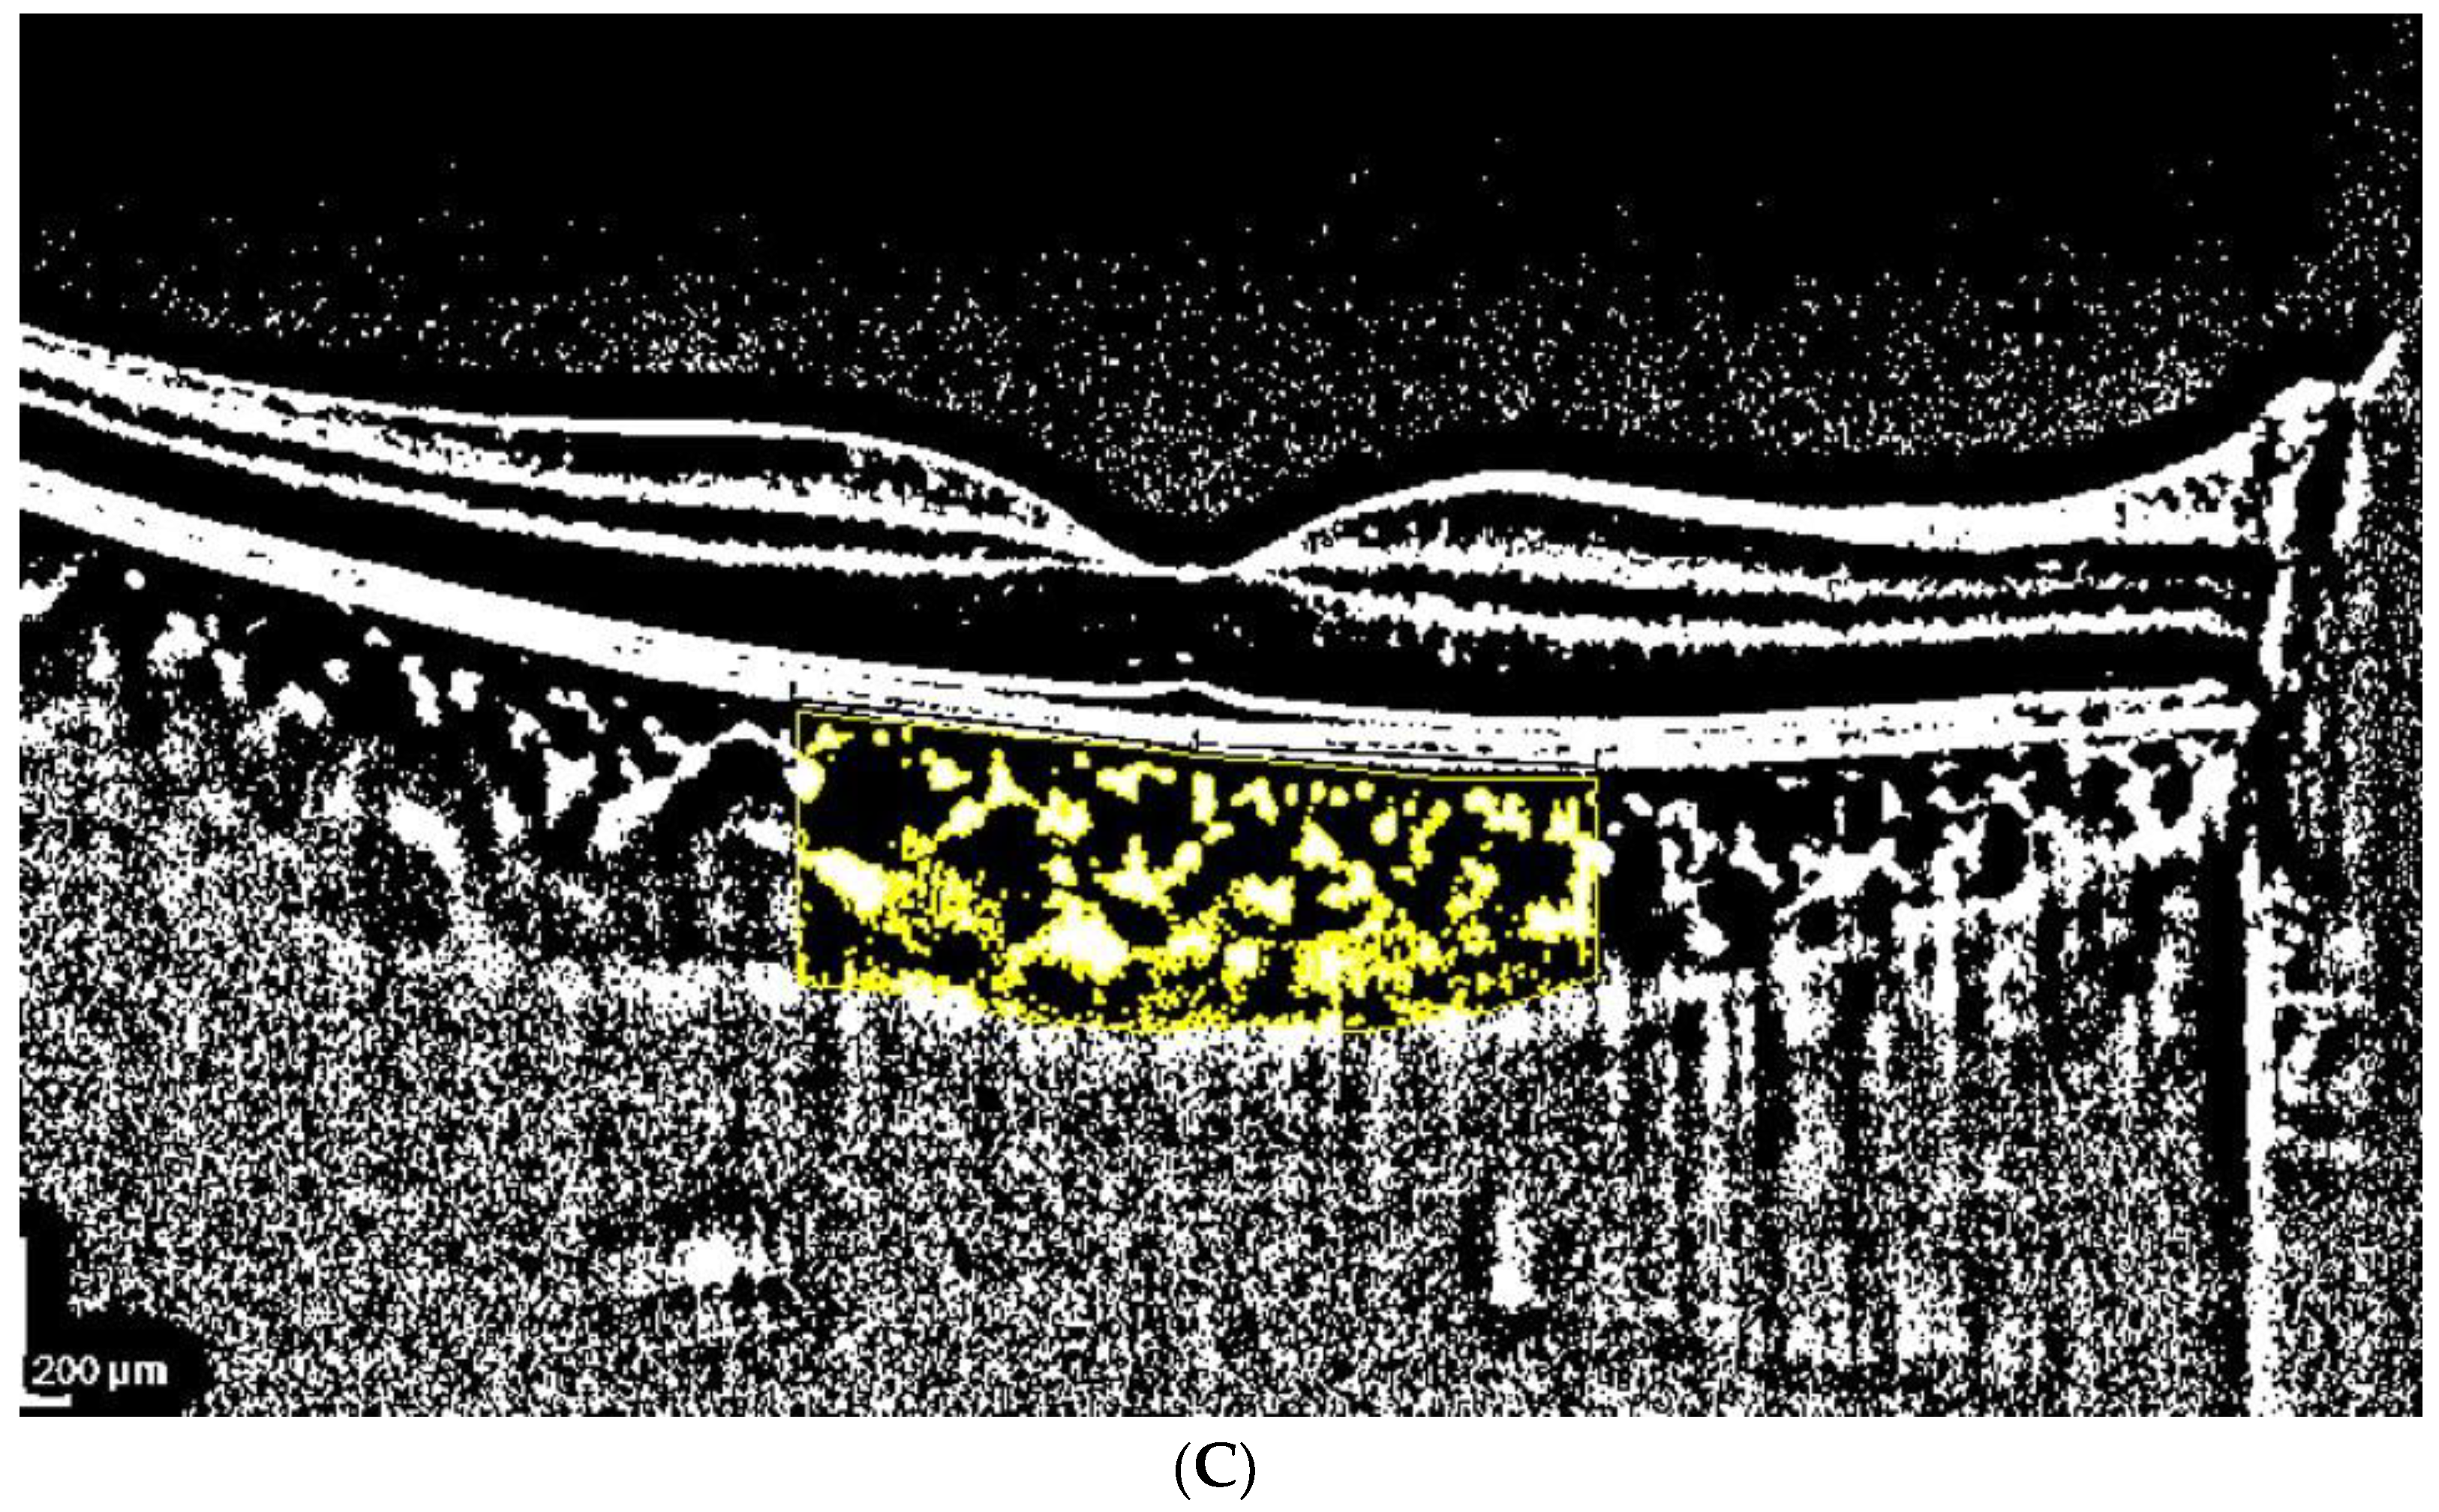

2.3. OCT Analysis

- A classic manual tracking method, manually drawing the lines to limit the choroidal area for each high and low brightness level [2].

- An alternative method, with a fixed area selection independent of the brightness level.